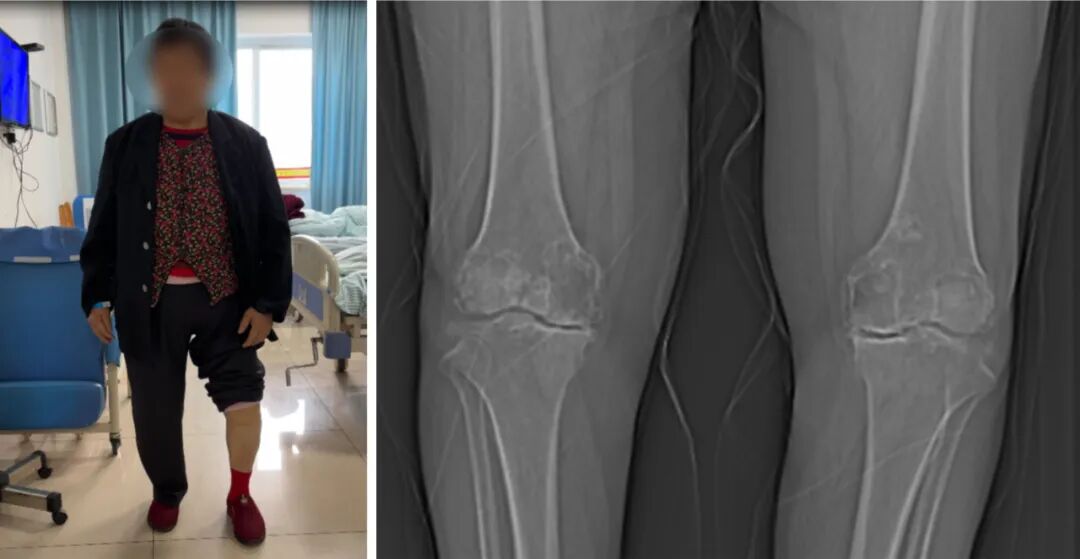

10多年前,赵阿姨双腿膝盖便开始胀痛,尤其是左侧关节处疼痛尤为明显,长时间的站立、爬楼梯时症状更为明显,为生活带来了诸多不便,但因早年没有正规干预,一直保守治疗效果不佳,导致疼痛反复发作且越来越严重,2年前双腿便出现不同程度的畸形,四处求医却始终未能寻得对症良方。后在朋友的推荐下,来到了彭州磊络福兴医院寻求救治。

医院骨科黄兴华主任与彭彬主任经过对病史的详细了解及相关检查,发现赵阿姨双膝关节骨质疏松明显,尤其是左侧,关节屈曲内翻畸形严重,因时间长久,关节软骨的磨损严重,目前已经无法通过保守治疗改善病情,建议通过外科手术治疗,即进行人工膝关节置换,以达到重建关节功能的目的。